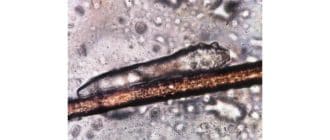

ダニはヒトに生息する一種の寄生虫です。ほとんどの場合、これらのダニは無害であり、気づかれなくなります。しかし、ダニの数が多いと、望ましくない症状や皮膚の問題を引き起こす可能性があります。 ダニは毛包の中または周囲に生息し […]